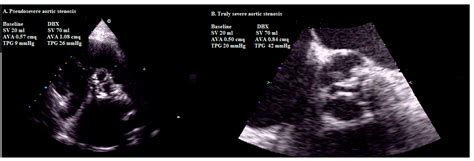

Physicians typically diagnose Severe Aortic Stenosis through a combination of physical examinations and advanced imaging technologies. The most common diagnostic tool is the echocardiogram, which provides a real-time visualization of the valve’s movement and measures the severity of the obstruction.

Transthoracic Echocardiogram (TTE) Valve area, pressure gradient, and left ventricular function.